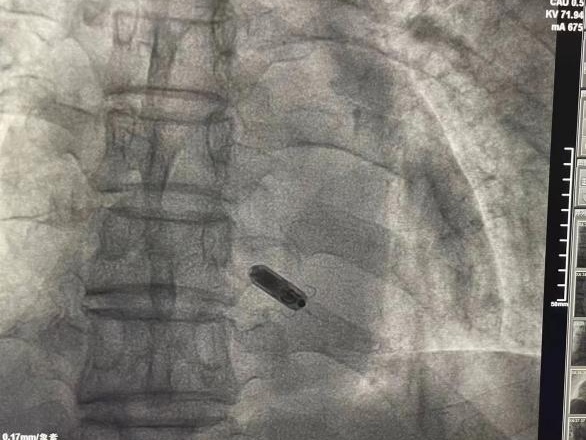

由于刘爹爹年龄偏大,基础病情复杂严重,肺部感染、全身状态较差,在分析了患者情况和充分考虑患者及其家属意愿后,湖北省中医院心内科介入团队为其制定了个体化起搏治疗手术方案,最终选择植入最新一代双腔无导线起搏器Micra AV。

无导线起搏器是起搏领域的重大突破。新一代的Micra AV无导线起搏器体积仅有胶囊大小,重约2克,不仅兼容1.5 T/3.0 T全身核磁共振扫描检查。虽然体积只有传统起搏器的十分之一,但其续航时间可达10-12年。

手术采用微创方式,以右侧股静脉作为“运输通道”,通过导管将这枚“胶囊”送达至刘爹爹的右心室,整个手术用时仅一个小时。手术次日,刘爹爹已可以下床正常活动,经测试,起搏器各项参数正常。